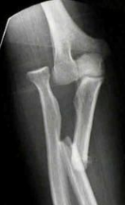

Mecanismo de lesion de esta fractura

Mecanismo INDIRECTO

Caida sobre la mano extendida con el codo en flexion

Se produce por avulsion de una parte de la apofisis por una contraccion del triceps

Mecanismo DIRECTO

Golpe directo al codo por caida o trauma

Tipo de fractura en la clasificacion de Mayo

1a (no desplazada, no conminutada)

2a (Desplazada estable, no conminutada)

3b (Desplazada inestable (por la luxacion) y conminutada)

Tratamiento de esta fractura

Conservador

Inmovilizar con yeso o ferula a 45-90°, inicio gradural de movilizacion a las 4 semanas

Obenque con clavillos de kirschner y alambre

Trtamiento de esta fractura

Fijacion con placa y tornillos (por multifragmentada)